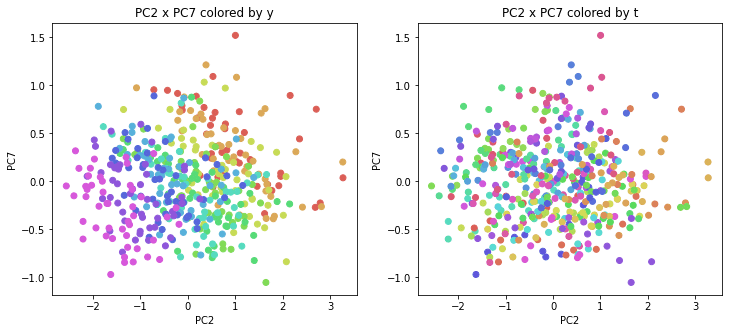

PCAの結果の第n主成分をPCnと表記します。

医療費データの場合と同様に、PCAの結果を見やすく表示するため、seabornのカラーパレットを使って、年月別、都道府県別に色分けして図示してみます(左側が年月別に色分け、右側が都道府県別に色分け)。PC1~PC8まで表示しました。

医療費データの場合ほどはっきりとはしていませんが、PC2が概ね時間の経過を表す成分で、残りの成分が時点によって変わらない地域の特徴を表す成分となっているようです。

また、PC1×PC3を見ると、47沖縄が他の都道府県からかなり離れたところに位置しており、沖縄の地域差が際立っているのが分かります。これは、以前別の記事で年齢階級のない健診データでPCAを実行した場合と似た結果となっています。

今回は、医療費データと同様に、健診データ240次元についてPCAを実行してみました。PCAの結果、医療費データの場合ほどはっきりしとはしていませんが、第2主成分が概ね時間の経過を表す成分で、時間軸に沿った全体的な動き(全国的な動き)を表しており、それ以外の成分が地域の特徴を表す成分で、この10年間あまり変わっていないことがわかりました。